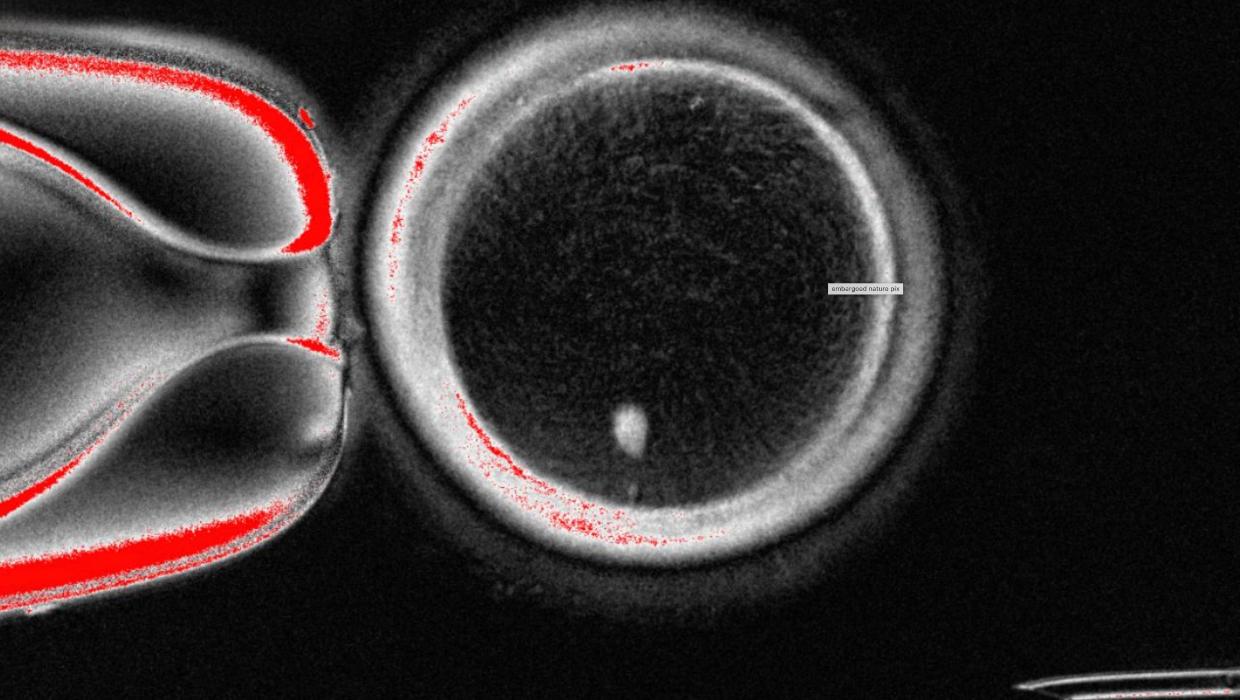

A team of scientists from the United States has successfully transformed human skin cells into fertilizable eggs, marking a significant milestone in reproductive science. This groundbreaking research, conducted at the University of California, Los Angeles (UCLA), offers new possibilities for developing lab-grown eggs and sperm, potentially aiding individuals facing fertility challenges.

The findings, published in the prestigious journal Nature, detail how researchers utilized a process called cellular reprogramming. By manipulating skin cells, they were able to create oocytes, which are immature eggs that can be fertilized. This innovative approach not only demonstrates the potential for creating gametes from non-reproductive tissue but also raises questions about the future of reproductive technologies.